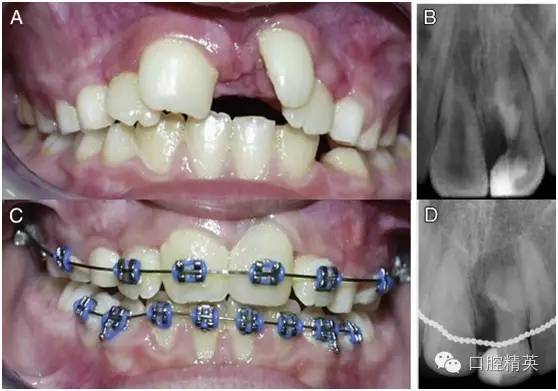

正常隨訪 12 周之后,患牙未出現(xiàn)異常癥狀(圖 3-A),于是按計(jì)劃開始對(duì)患者進(jìn)行牙齒的矯正。從骨頭和牙齒來看,患者都表現(xiàn)出了遠(yuǎn)中錯(cuò)頜的關(guān)系,按照安氏分類法,患者被診斷為安氏 2 類 1 分類錯(cuò)頜畸形?;颊哳M骨發(fā)育基本正常,上頜稍后縮,但未出現(xiàn)反頜。上頜切牙區(qū)稍擁擠。

圖 3 正畸前與正畸后期資料。(A)正畸前口內(nèi)像,此時(shí)多生牙部分已被切除,露髓處已經(jīng) MTA 蓋髓,且正常隨訪一段時(shí)間后未見其他異常癥狀出現(xiàn)。(B)正畸前患牙根尖片。(C)正畸治療將要結(jié)束時(shí)的口內(nèi)像,此時(shí)患牙牙冠已經(jīng)參照右上中切牙用復(fù)合樹脂進(jìn)行了美學(xué)修復(fù)。(D)正畸后患牙根尖片。

整個(gè)正畸過程持續(xù)了 3 年半(圖 3-C)。正畸完成治療后,為了獲得最終的美學(xué)效果,患牙剩余部分參照右上中切牙的外形和顏色用樹脂做了充填修復(fù)(圖 3-C)。將術(shù)前根尖片(圖 3-B)與正畸后根尖片(圖 3-D)相比較可以發(fā)現(xiàn),患牙最終表現(xiàn)出了良好的治療效果。